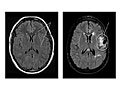

Magnetic resonance imaging (MRI) is a test that uses a magnetic field and pulses of radio wave energy to take pictures of the head. In many cases, MRI gives information that can't be seen on an X-ray, ultrasound, or computed tomography (CT) scan.

For an MRI of the head, you lie with your head inside a special machine (scanner) that has a strong magnet. The MRI can show tissue damage or disease, such as infection or inflammation, or a tumor, stroke, or seizure. Information from an MRI can be saved and stored on a computer for more study. Photographs or films of certain views can also be made.

Magnetic resonance imaging (MRI) is a test that uses a magnetic field and pulses of radio wave energy to take pictures of the head.

Magnetic resonance imaging (MRI) of the head